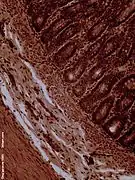

Histology

The jejunum contains very few Brunner's glands (found in the duodenum) or Peyer's patches (found in the ileum). However, there are a few jejunal lymph nodes suspended in its mesentery. The jejunum has many large circular folds in its submucosa called plicae circulares that which increase the surface area for nutrient absorption. The plicae circulares are best developed in the jejunum.

- The villi of the jejunum look like long, finger-like projections, and are a histologically identifiable structure.

Dog jejunum (magnified 100-fold)